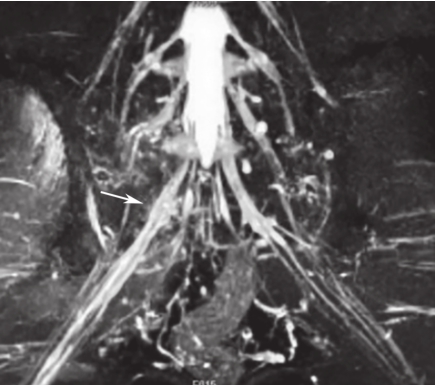

白靖平等认为用MRI扫描骶骨斜冠状面,当有骶神经损伤时,MRI图像显示骶神经周围脂肪组织消失,其直径变窄,且神经走向改变等。许道洲等则认为MRI平扫不能直接显示骶神经根的损伤,MRI SPACE-STIR序列扫描能提供三维TSE对比成像。在SPACE-STIR序列扫描图像上,在骨折周围出现下列征象时应考虑有神经根的损伤:①神经节后线状高信号走行中断,是诊断神经根损伤的直接征象,表现为神经根在骨折处呈截断征,如图2-15;②神经根走行发生改变,是诊断神经根损伤可靠的间接征象,表现为神经根自然走行弧度消失,在骨折处呈弧形受压移位改变,甚至出现成角改变,如图2-16;③神经异常肿胀增粗,是诊断神经根损伤的间接征象,表现为骨折附近神经明显较近端及远端增粗,如图2-17。

图2-16 右侧骶骨骨折,SPACE-STIR序列MRI神经成像重建

可见骨折块自前向后推压S

1

神经根,神经根自然走行弧度消失,呈弧形移位改变(箭头所指)。